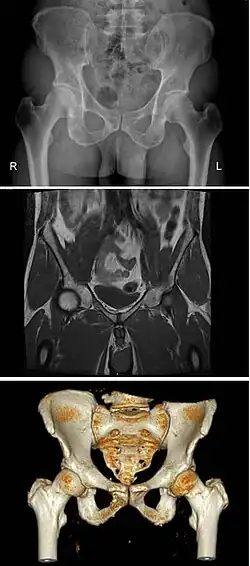

Różnice anatomiczne w budowie miednicy u mężczyzn i kobiet

Odmienności płciowe w budowie miednicy można zaobserwować już u płodu. Spojenie łonowe noworodka męskiego jest widocznie wyższe od żeńskiego. Jednak jednoznaczne i charakterystyczne różnice płciowe występują dopiero u osoby dojrzałej, gdyż w okresie pokwitania miednica kobiet jest dostosowywana do porodu.

Kobieca miednica posiada szeroko na boki rozstawione talerze kości biodrowych. U mężczyzn są one ułożone bardziej stromo. Kość krzyżowa kobiet jest stosunkowo szersza i bardziej płaska niż męska[1].